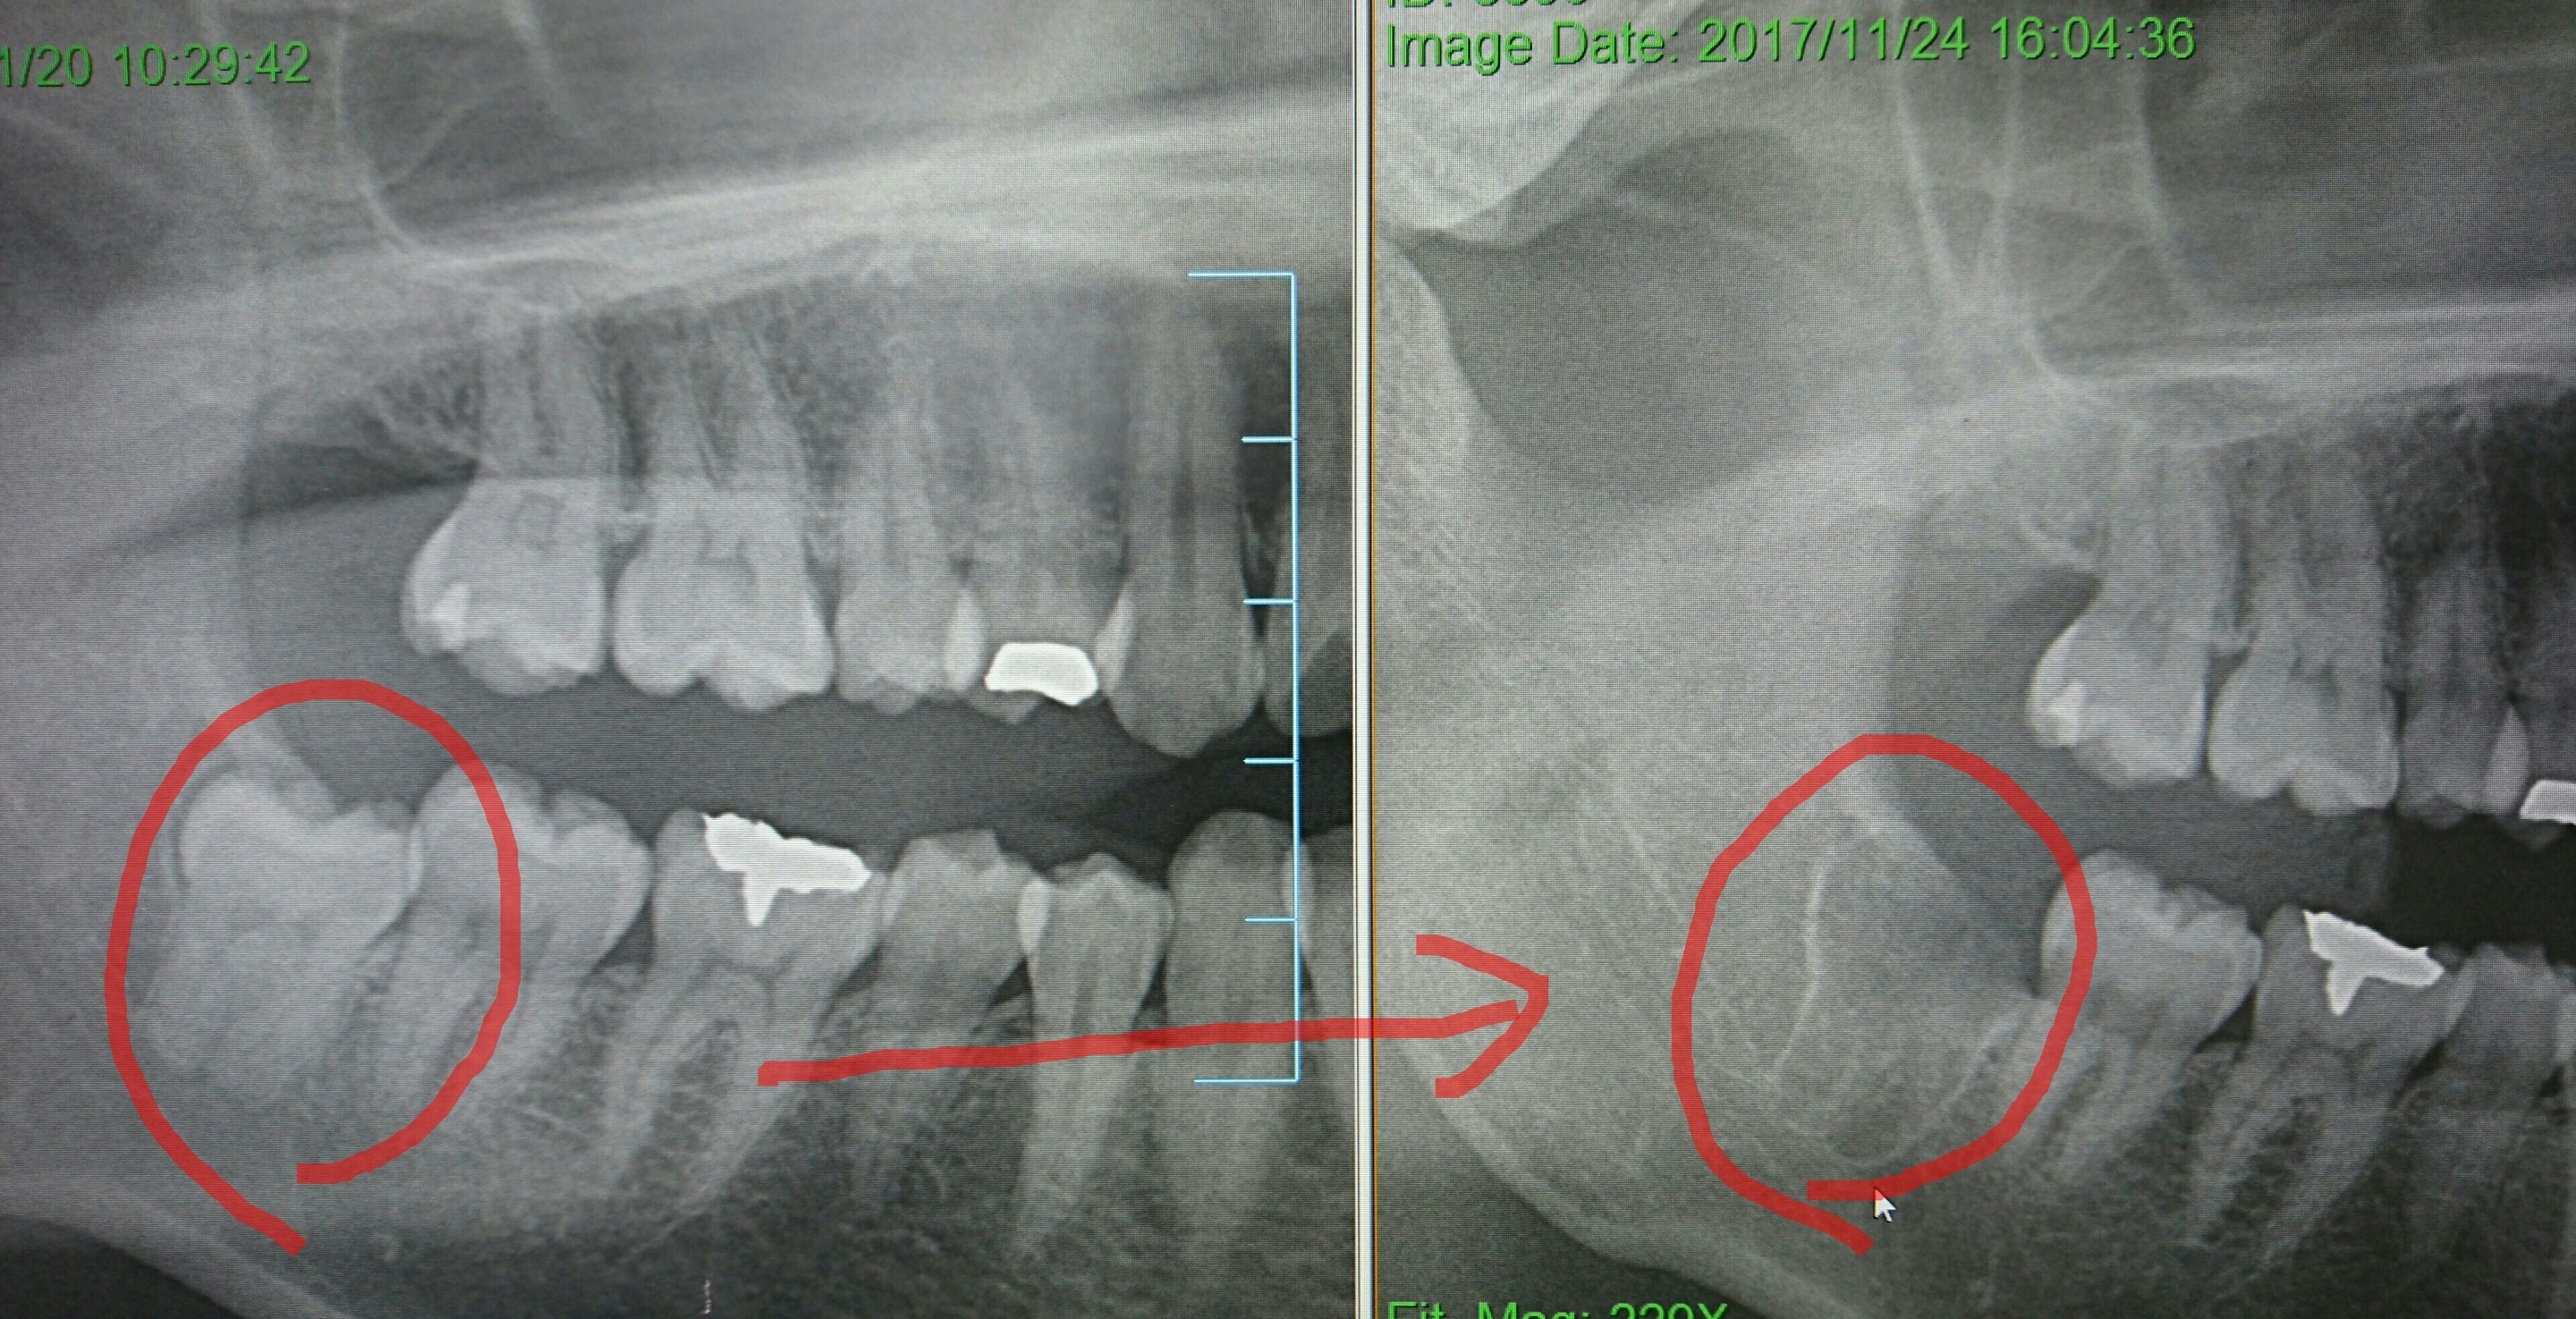

親知らずの抜歯にはCT画像が不可欠と言っても過言ではありません。従来のパノラマ画像(前回のブログの5症例)では2次元的な画像に対しCT画像は3次元画像なので、より精密に診査診断が可能になります。下記に輪切りにしたCT画像を掲載します。(ちなみにCTを導入している歯科医院は全国で20%程度です。当医院では2年前より医科歯科用コーンビームCTを導入しております。病院のヘリカルCTより撮影時間も短く(16秒)、被爆量も少ないのです)

(下記添付の輪切りのCT画像の説明)

(矢印↑)の先の(赤丸◯)の中に下歯槽神経と動脈が存在し、これを傷つけると大量出血や神経麻痺の可能性も。パノラマ画像では神経、動脈との位置関係がわかりずらいのですがCTは一目瞭然!

従ってここが肝心要❗(肝)

親知らずの抜歯は、「血管の損傷・組織の挫滅を最小限」にすれば、「痛み」「腫れ」「出血」もありません。加えて施術時間も麻酔時間を考慮し1時間以内(通常30分~40分)であれば尚更問題ありません。もちろん患者さんの体調あってのことですが。